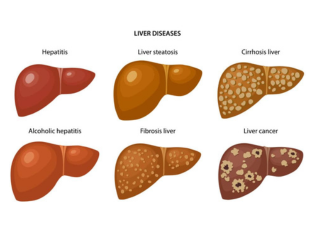

❈ What is Alcohol Liver Disease?

Drinking alcohol consistently in moderate amounts over 10 to 20 years can cause alcohol liver disease. There are 3 types of liver conditions:

- Fatty liver

- Alcoholic hepatitis

- Cirrhosis

❈ Fatty liver

Accumulation of fat within liver cells in most people who drink regularly. Fatty liver usually causes no symptoms and is completely reversible if one stops drinking alcohol. However in some who continue to drink this can progress into hepatitis.

❈ Alcoholic hepatitis

It simple means inflammation of the liver. Ÿ Mild: Usually no symptoms, detected by blood tests showing abnormal liver enzymes. If this is persistent it can gradually damage the liver resulting in cirrhosis. This form of hepatitis can recover if one stops drinking completely. Ÿ Severe hepatitis: This tends to cause symptoms such as nausea, vomiting pain in the upper abdomen, jaundice( yellowing of the skin caused by high bilirubin level). In some cases this can lead to liver failure associated with clotting problems, bleeding, confusion , coma and can be fatal. Patients usually require admission and monitoring in hospital with complete abstinence from alcohol, proper nutrition along with supportive medical treatment. Some cases may need steroids or other antiinflammatory medication like pentoxyphylline. Unfortunately severe hepatitis has a poor outcome with only 50% chance of surviving beyond 3 months.

❈ Alcoholic Cirrhosis

Cirrhosis means scarring of liver, whereby normal liver tissue is replaced by scarred tissue(fibrosis). The liver becomes shrunken. This happens gradually if the liver tissue is inflamed for a long period of time. The liver is usually able to repair itself with complete abstinence from alcohol, however it never recovers completely. By stopping drinking you can prevent further damage to your liver and reduce risk of decomposition . This term is often used by liver specialist to suggest onset of complications from poor liver function. The following complications can be potentially fatal.

- Jaundice( yellow discolouration of eyes),

- Ascites(swollen belly due to water retention),

- Hepatic encephalopathy (confusion),

- vomiting of blood from varices (swollen internal veins)

- Liver cancer

- Hepatorenal syndrome: (poor kidney function due to liver disease)

- Malnutrition(poor intake of vitamins, minerals, protein from loss of appetite)

Most patients will require liver transplantation if there is no improvement in liver function after a period of abstinence from alcohol.

❈ Non-alcoholic Fatty Liver Disease and Non-Alcoholic Steatohepatitis

Non-alcoholic fatty liver disease (NAFLD) is a condition in which fat builds up in the liver. In some cases this accumulation of fat can cause inflammation of the liver and eventually lead to permanent scarring (cirrhosis), which can seriously impair the liver’s ability to function. Unlike alcoholic fatty liver disease (alcoholic steatohepatitis), NAFLD can occur in people who drink no alcohol or drink only in moderation. NAFLD is, however, closely associated with obesity and diabetes. The consequences of the condition can be grave and NAFLD represents a major global public health problem.

❈ How to diagnose NAFLD?

A healthy liver contains very little or no fat. NAFLD occurs in people who do not drink a significant amount of alcohol (20 grams per day for men and 10 grams per day for women) and who do not have a viral infection or other specific cause of liver disease. NAFLD is diagnosed when accumulation of fat in the organ exceeds 5% of hepatocytes (the cells that make up the majority of the liver). NAFLD is sometimes called a ‘silent disease’ as even in its late stages it may have no symptoms and may only be diagnosed after liver function tests have revealed an abnormality.

❈ Diagnosis:

- Blood test (AST and ALT usually elevated)

- Imaging: Usually presence of fat seen on ultrasound, CT scan or MRI

- Liver biopsy

- Liver fibroscan (non-invasive test) has replaced liver biopsy in majority of case

❈ What are the stages of NAFLD and treatment options?

From simple fatty liver to irreversible cirrhosis NAFLD can progress from steatosis, to non-alcoholic steatohepatitis (NASH), to fibrosis and then to cirrhosis. Effective treatment options in NAFLD include weight reduction, dietary changes and physical activity. In its early stages, NAFLD can be treated through diet and lifestyle changes, such as losing weight. Cirrhosis, the most severe stage of NAFLD, usually only occurs after years of liver inflammation and can lead to a range of complications, including liver failure and hepatocellular carcinoma (HCC). Between 10 and 30% of patients with NAFLD have NASH that can progress to cirrhosis.

❈ What are the risk factors for developing NAFLD?

NAFLD is usually seen in people who are overweight or obese. Those with insulin resistance, type 2 diabetes, high blood pressure or high blood lipids (cholesterol and triglycerides) are also more likely to develop NAFLD. Studies have reported NAFLD prevalence rates of between approximately 43 and 70% in adults with type 2 diabetes. Obesity and diabetes are on the rise around the world. Obesity triggers inflammatory pathways in the brain and adipose tissue, resulting in the disruption of insulin levels. Over time, fat accumulates in the liver (as well as muscles and blood vessels), which exacerbates systemic insulin resistance.

❈ The heavy toll of NAFLD

NAFLD increases the risk of overall mortality and of mortality related to cardiovascular disease and liver disease. Controlling the etiological factors helps to reverse the condition as long as there is no permanent scarring in the liver. Persistent inflammation can cause scarring and cirrhosis.